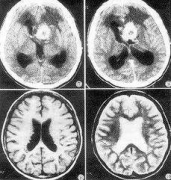

脑海绵状血管瘤突变检测在家族

脑海绵状血管瘤(CCM)是一种少见的常染色体显性遗传疾病,其外显...